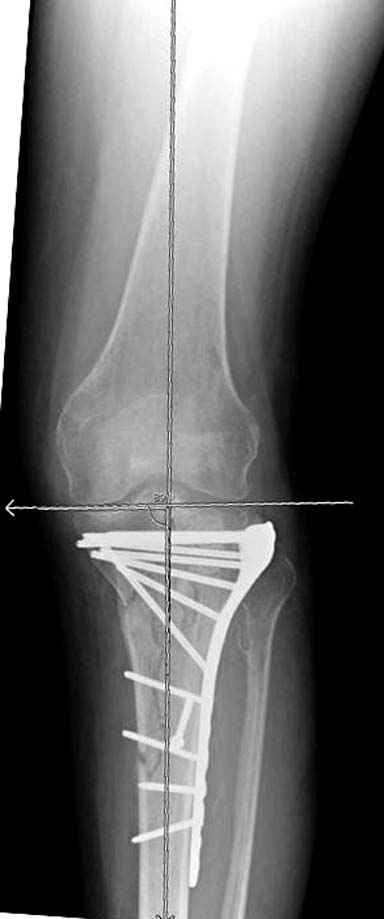

Решили выполнить остеосинтез штифтом и внутрисуставного перелома пластиной и винтами. Жду мнения! Зачем мне оправдываться-я же не преступник. Диалогом называется...

При переломах одного из мыщелков тибиал плато+дополнительный перелом проксимальной трети большеберцовой кости можно применить комбинированный вариант фиксации, т.е. мыщелок винтами или пластиной, а для диафиза можно установить гвоздь. В данном варианте потеряно преимущество гвоздя , из-за серьезной травмы суставной поверхности нельзя нагружать ногу несколько месяцев. А без нагрузки гвоздь просто заполнитель пространства внутри кости!

На вашем место я бы подождал с фиксацией до готовности кожных покровов, и за это время можно было подобрать соответствующий фиксатор, т.е более длинная пластина снаружи и медиальная пластина на апексе перелома как подпорка. Здесь приемлем как раз минимальный доступ.

Имеющаяся импрессия не потребовала пластики - достаточным оказалось поднять отломок

Если там действительная импрессия, пустое место без структуральных заполнителей, кость или синтетические материалы, не восстановится, а образуется коллапс, и ось конечности поведет после нагрузки. Кроме того там возможно "болт стяжка"?, в медиальной стороне выступает за кортекс, можно было укоротить! Потом создается впечатление, что не соответствуют мыщелки большеберцовой и бедренной костей? Покажите снимок.

Здесь пару случаев для сравнения,...в первых 1-4 слайдах метод фиксации одним фиксатором, как видно после 8 месяцев сохранилась ось. С 5 по 9 вариант двумя пластинами...